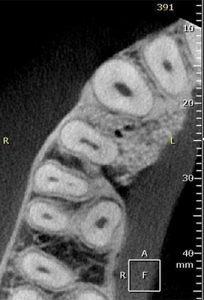

18, 19 e 20 | Diferentes planos tomográficos, evidenciando o preenchimento do defeito com biomaterial e a regeneração óssea.